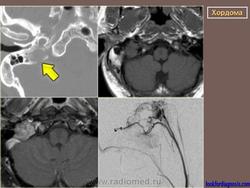

Хотя хордома может возникнуть в любом отделе позвоночного столба, наиболее излюбленными местами локализации этой опухоли являются 1-й шейный позвонок и пояснично-крестцовый отдел позвоночника. Это достаточно редкое заболевание. Чаще всего хордома возникает у мужчин среднего возраста. По данным рентгенографии, компьютерной томографии, магнитно-резонансной томографии можно поставить только предварительный диагноз. Для подтверждения диагноза необходимо проведение биопсии (забор кусочка опухолевой ткани с проведением микроскопического исследования). Лечение хирургическое. Прогноз зависит от размеров опухоли, наличия осложнений и общего состояния пациента.

Хордома развивается из персистирующих остатков хорды. Преимущественная локализация хордомы - это область сфеноокципитального сочленения и крестцово-копчиковый отдел позвоночника. Сведения о частоте отдельных форм хордомы весьма разноречивы.

Рентгенологическая картина хордом характеризуется наличием очага деструкции, захватывающего ряд позвонков. Костный дефект представляется однородным, либо крупнокамерным за счет тонких костных полосок. Показаны боковые рентгенограммы крестца, на которых при хордоме определяется увеличение передне-заднего размера крестца за счет экспансивного роста опухоли. В отдельных случаях в опухоли прослеживаются небольшие костные включения, которые могут служить поводом для ошибочной диагностики тератом, особенно в детском возрасте. (В детском возрасте тератомы встречаются часто, их соотношение с хордомами, по данным М. В. Волкова, 60:2).

Для хордом различных локализаций, выявлены наиболее характерные симптомы. Так, селлярные хордомы чаще проявляются глазодвигательными нарушениями (III нерв - 43%, VI нерв - 59%), и у трети больных эндокринными нарушениями (чаще гипотиреоз, гипокортицизм, гипогонадизм). У больных с хордомами ската типичными симптомами были поражение отводящего (79%), тройничного нерва (65%) и туловищная атаксия (55%). Симптомы поражения VII, VIII, IX или X черепных нервов были у трети больных с этой локализацией опухоли. Клиника при локализации хордом в краниовертебральной области представлена, как правило, характерным симптомокомплексом. Поражаются черепные нервы с VI по XII (VI -53%, VII - 33%, VIII - 27%, IX и X - 77%, XI - 48%, XII - 62%), у части больных имеют место тетрапарез или гемипарез. Нередко обращает на себя внимание вынужденное положение головы или ограничение объёма движений (поворотов и наклонов головы), боль и "хруст" в шее.